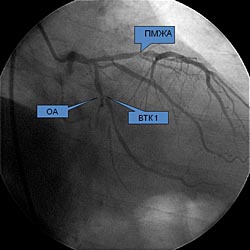

Поступил в НЦГиССХ им. Св Георгия для проведения обследования и решения вопроса об оперативном лечении. При коронарографии выявлено критическое поражение венечного русла: Тип кровоснабжения правый. Ствол ЛКА - стеноз до 20%, ПМЖВ - стеноз до 75%. ОА - устьевой стеноз 50%, ВТК1 - устьевой стеноз 95% и в средней трети - 90%, ПКА - стеноз в среднем и дистальном сегментах до 85%. (рис. 1,2). По данным дуплексного сканирования брахиоцефальных артерий (БЦА) выявлен стеноз правой внутренней сонной артерии (рис. 3).

Рис. 1 |